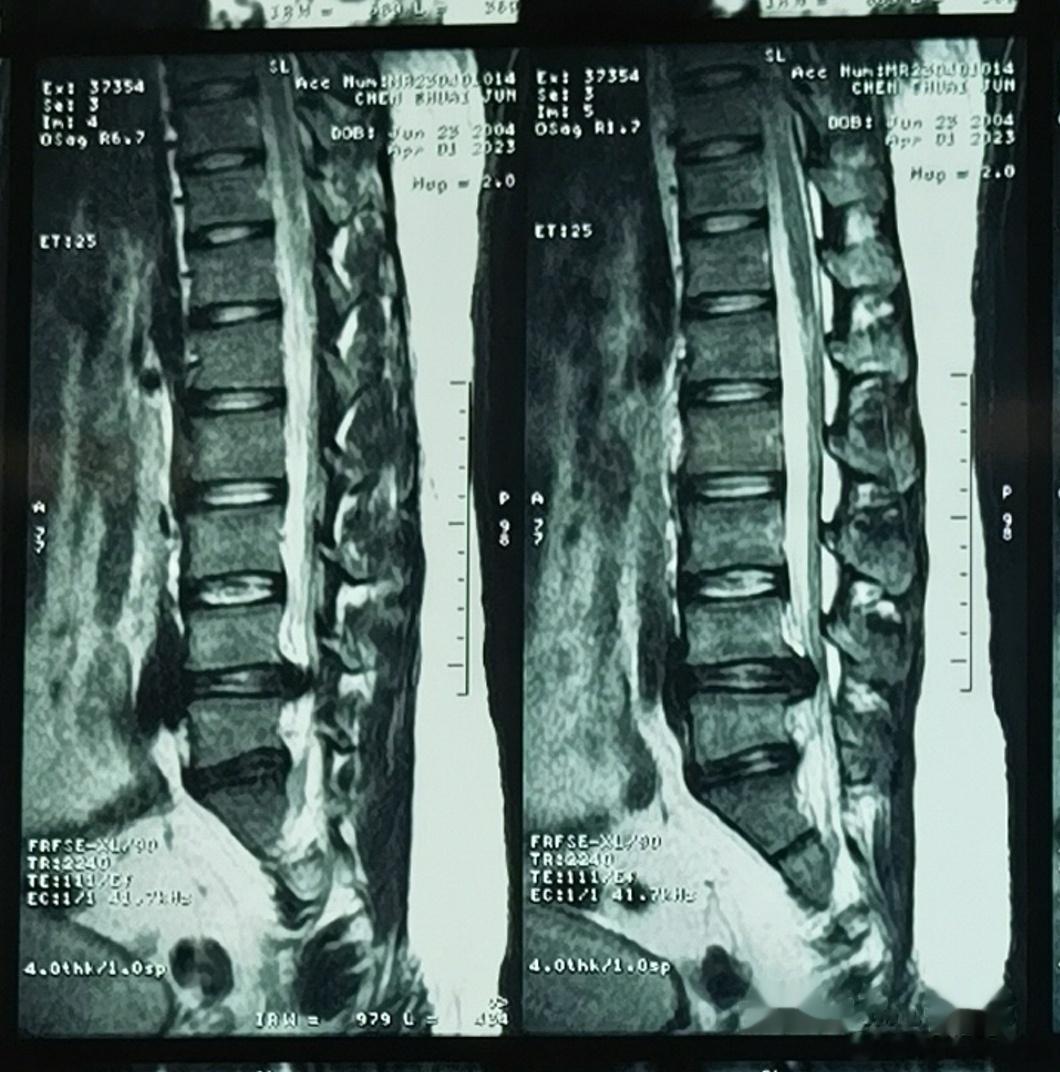

可怜的小胖孩子,一个喷嚏把自己打废了。椎间盘突出这么多,18岁大男孩,疼的哭😭

2023-04-03 20:50